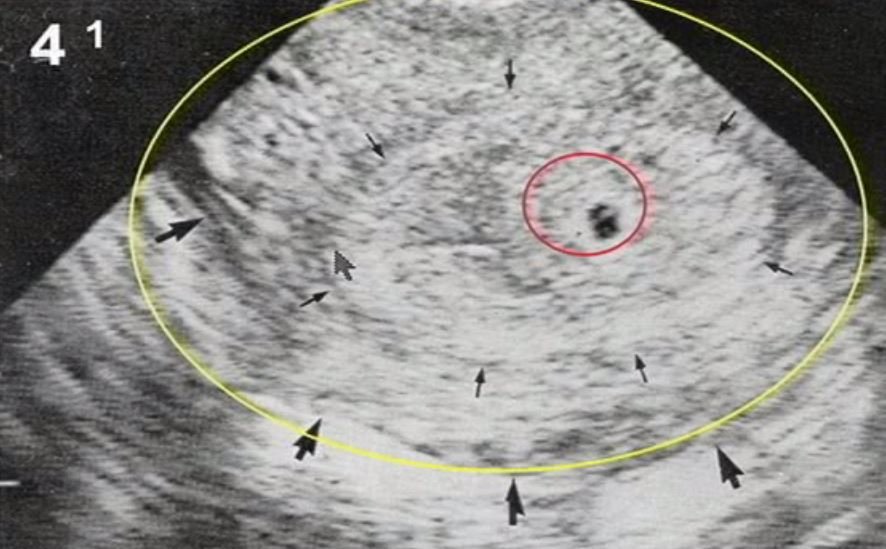

VEamos unos ecos

aborto retenido

1